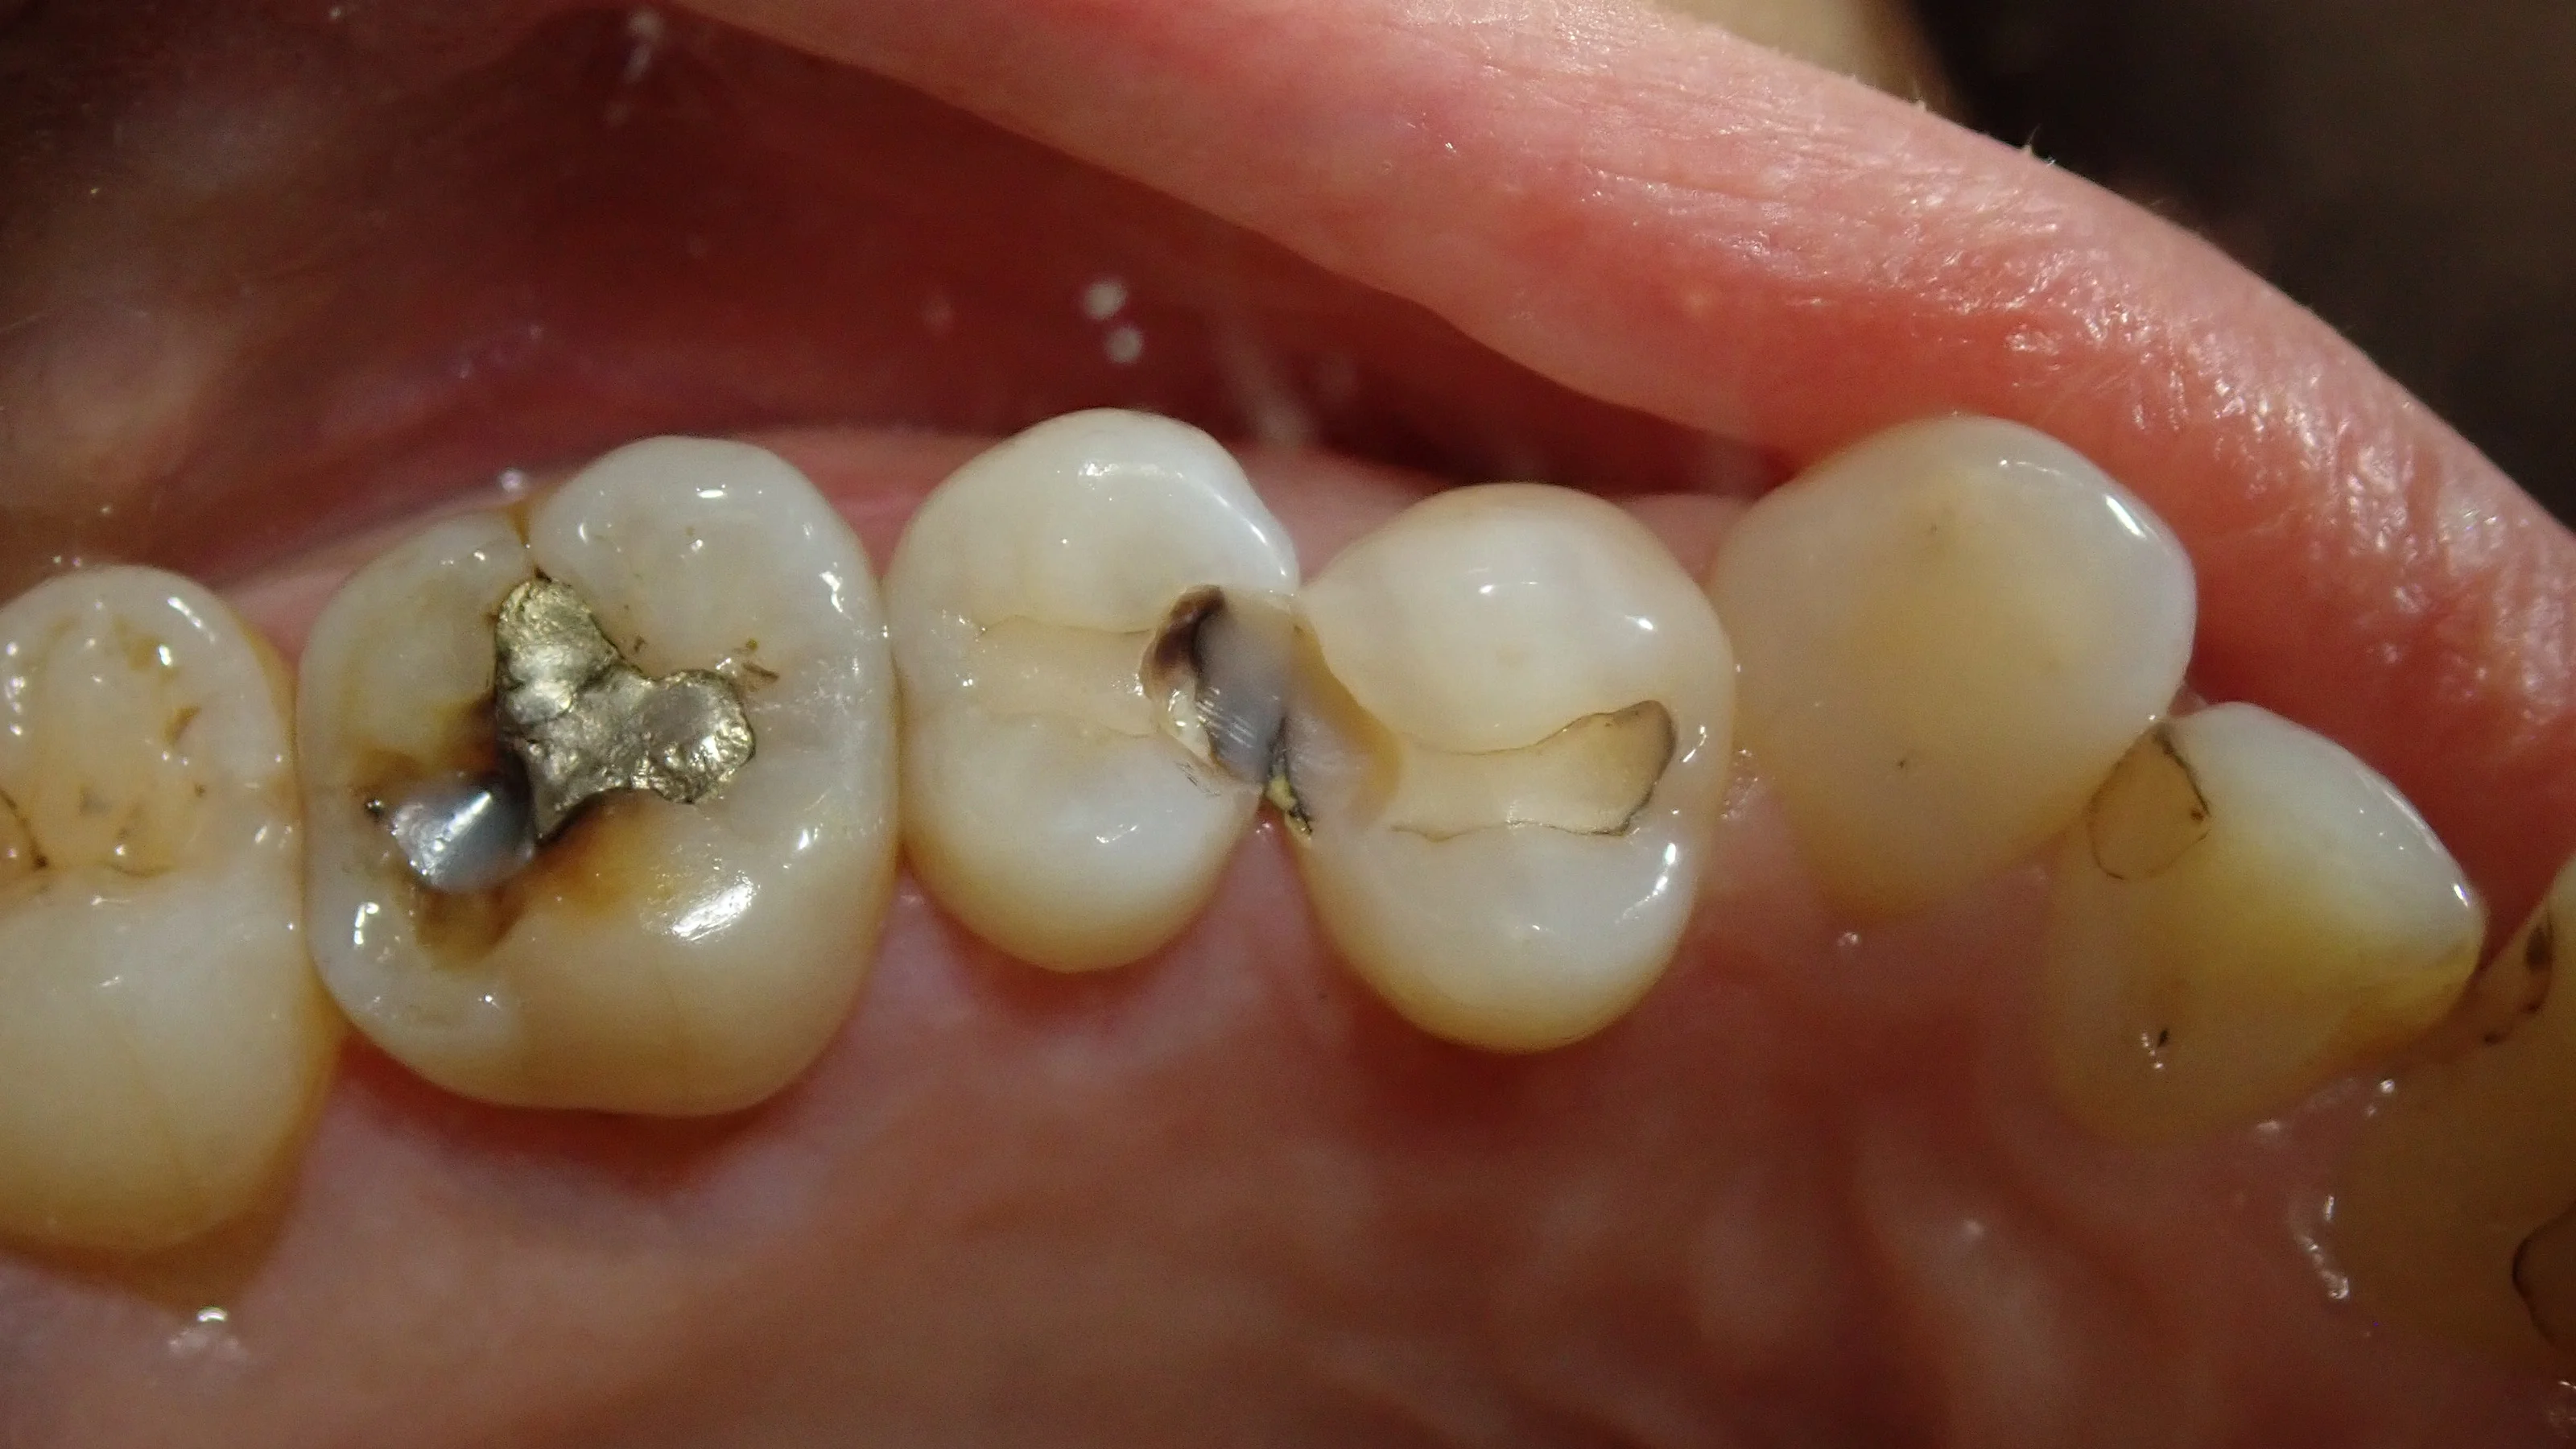

まずはいつもどおり術前から。

今回行うのは画面真ん中の2本の虫歯になります。

元々治療されている白い詰め物の中が黒っぽくなっているのが分かるかと思います。